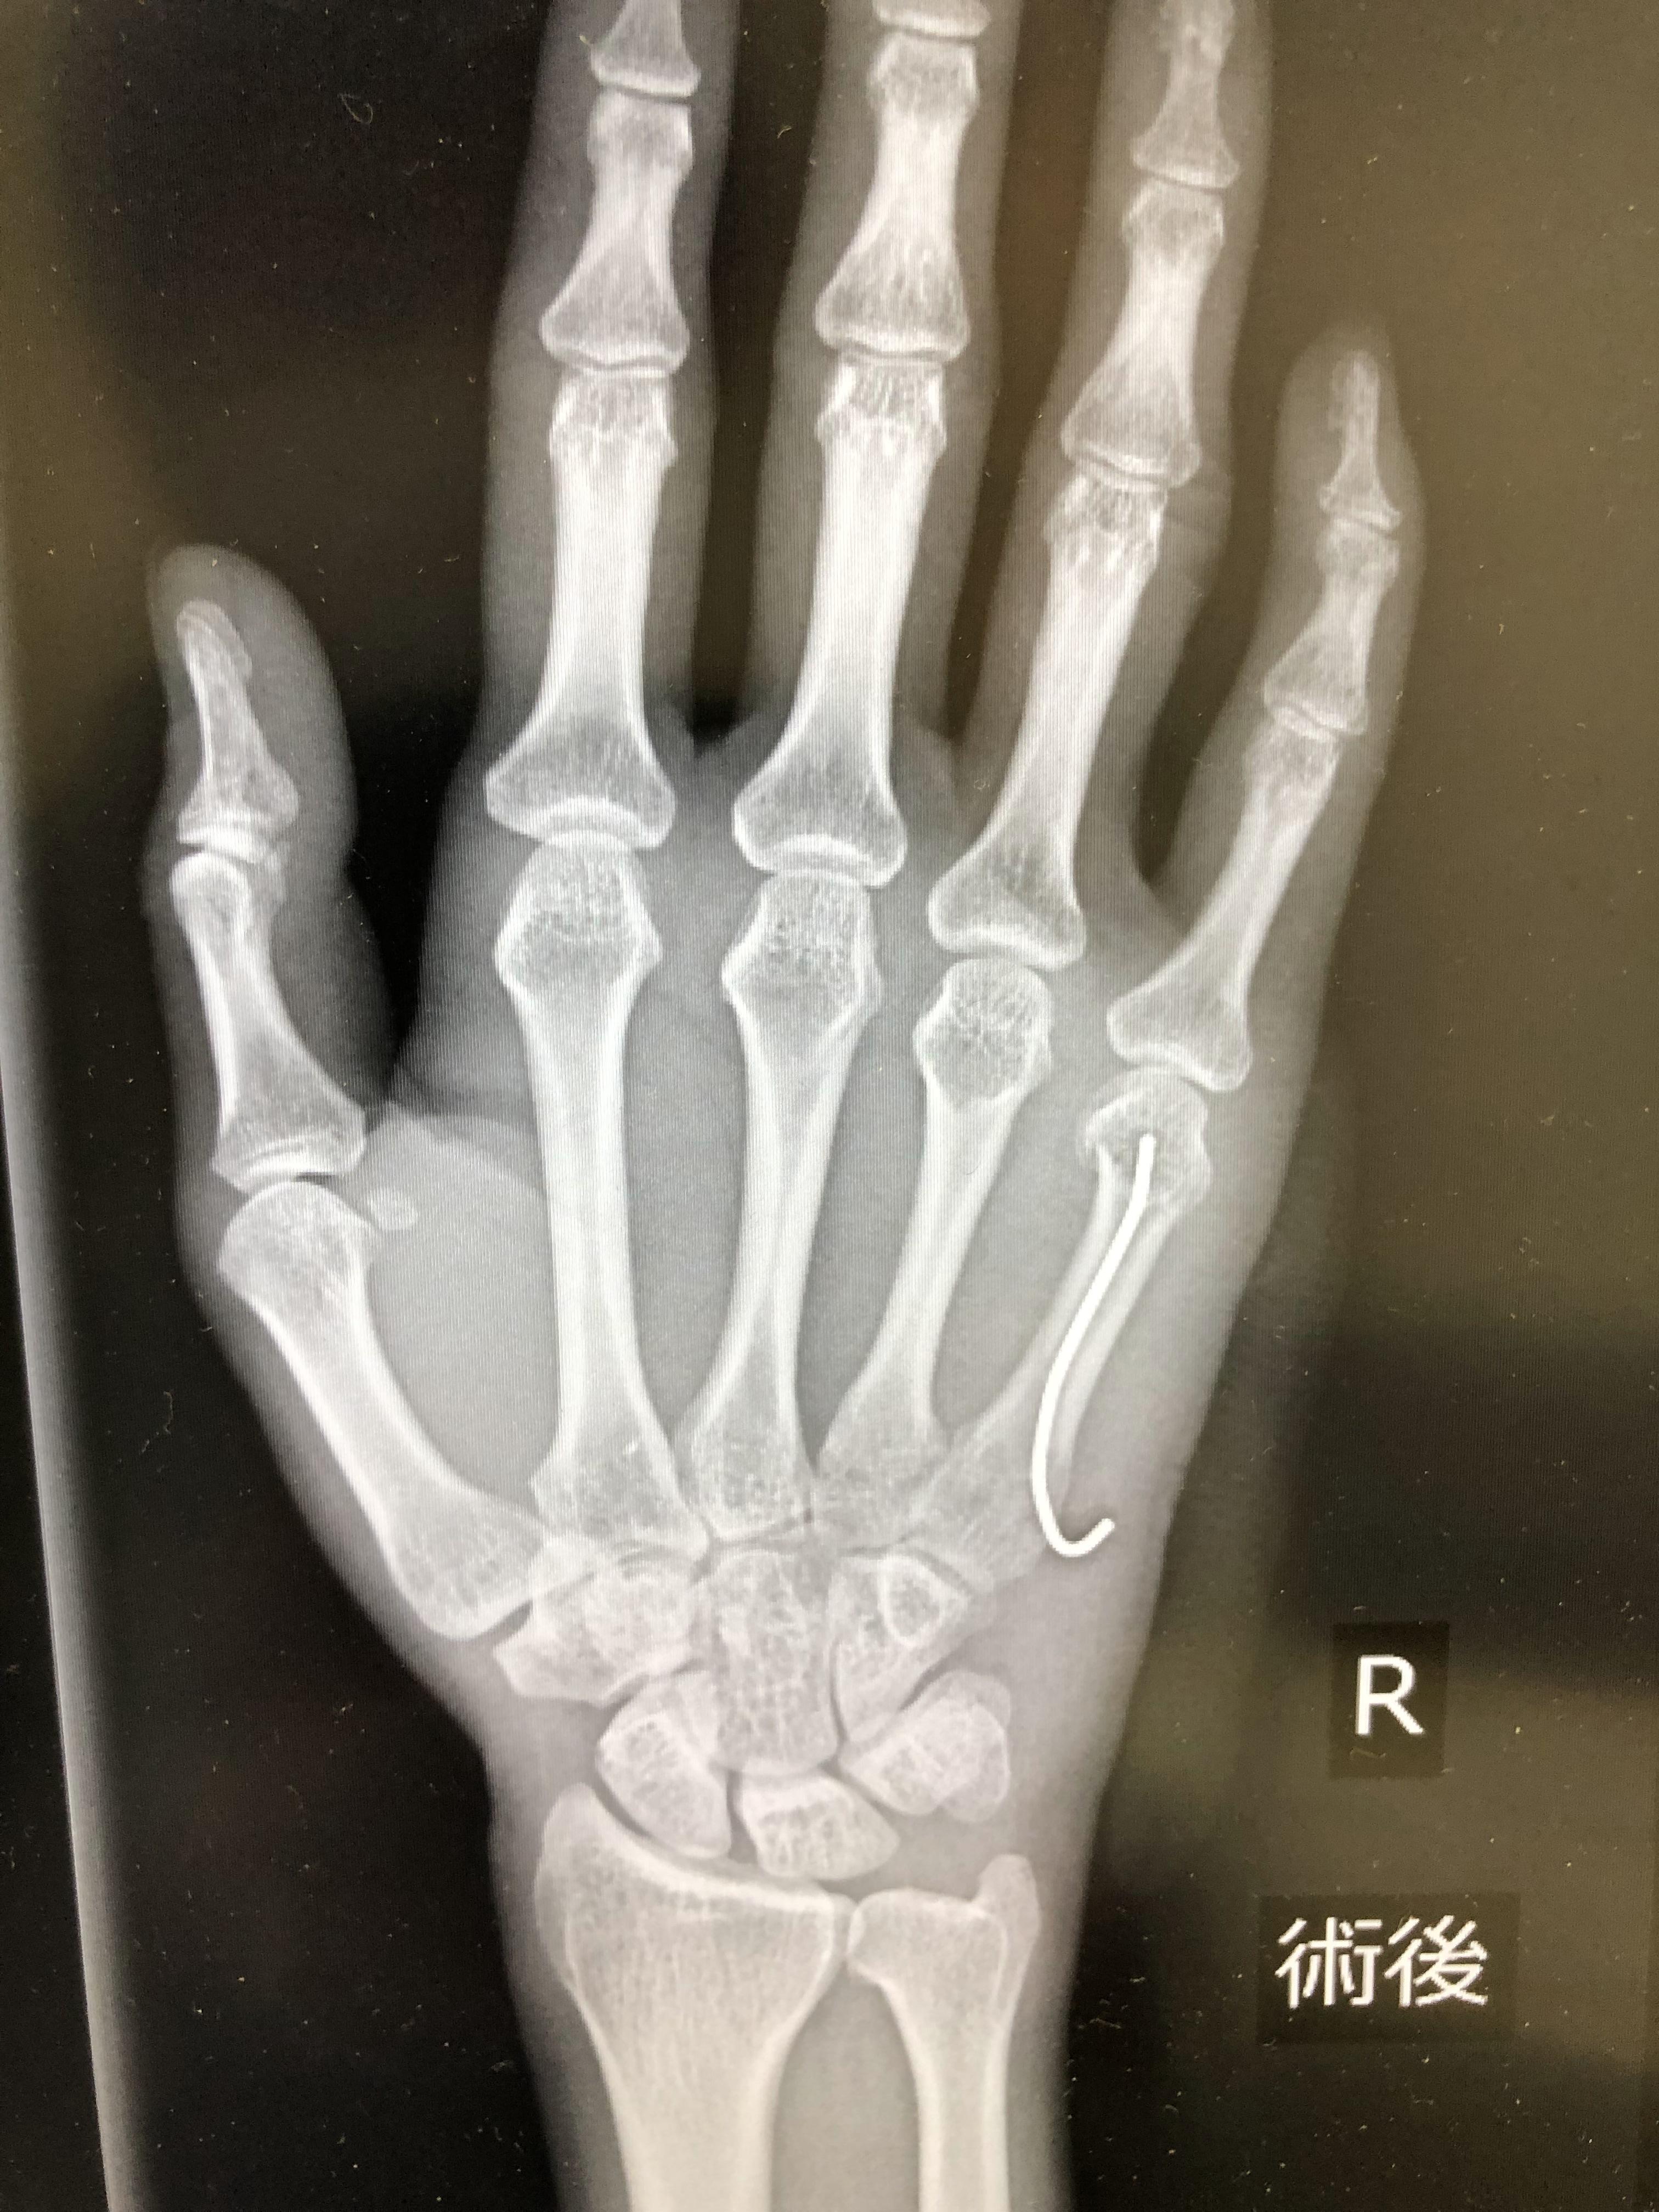

어찌저찌하다가 새끼손가락 뼈가 휘여서 철심을 박았습니다. ㅠ.ㅠ

보이시나요? 새끼손가락 안에 들어간 저 철심 ㅠ.ㅠ